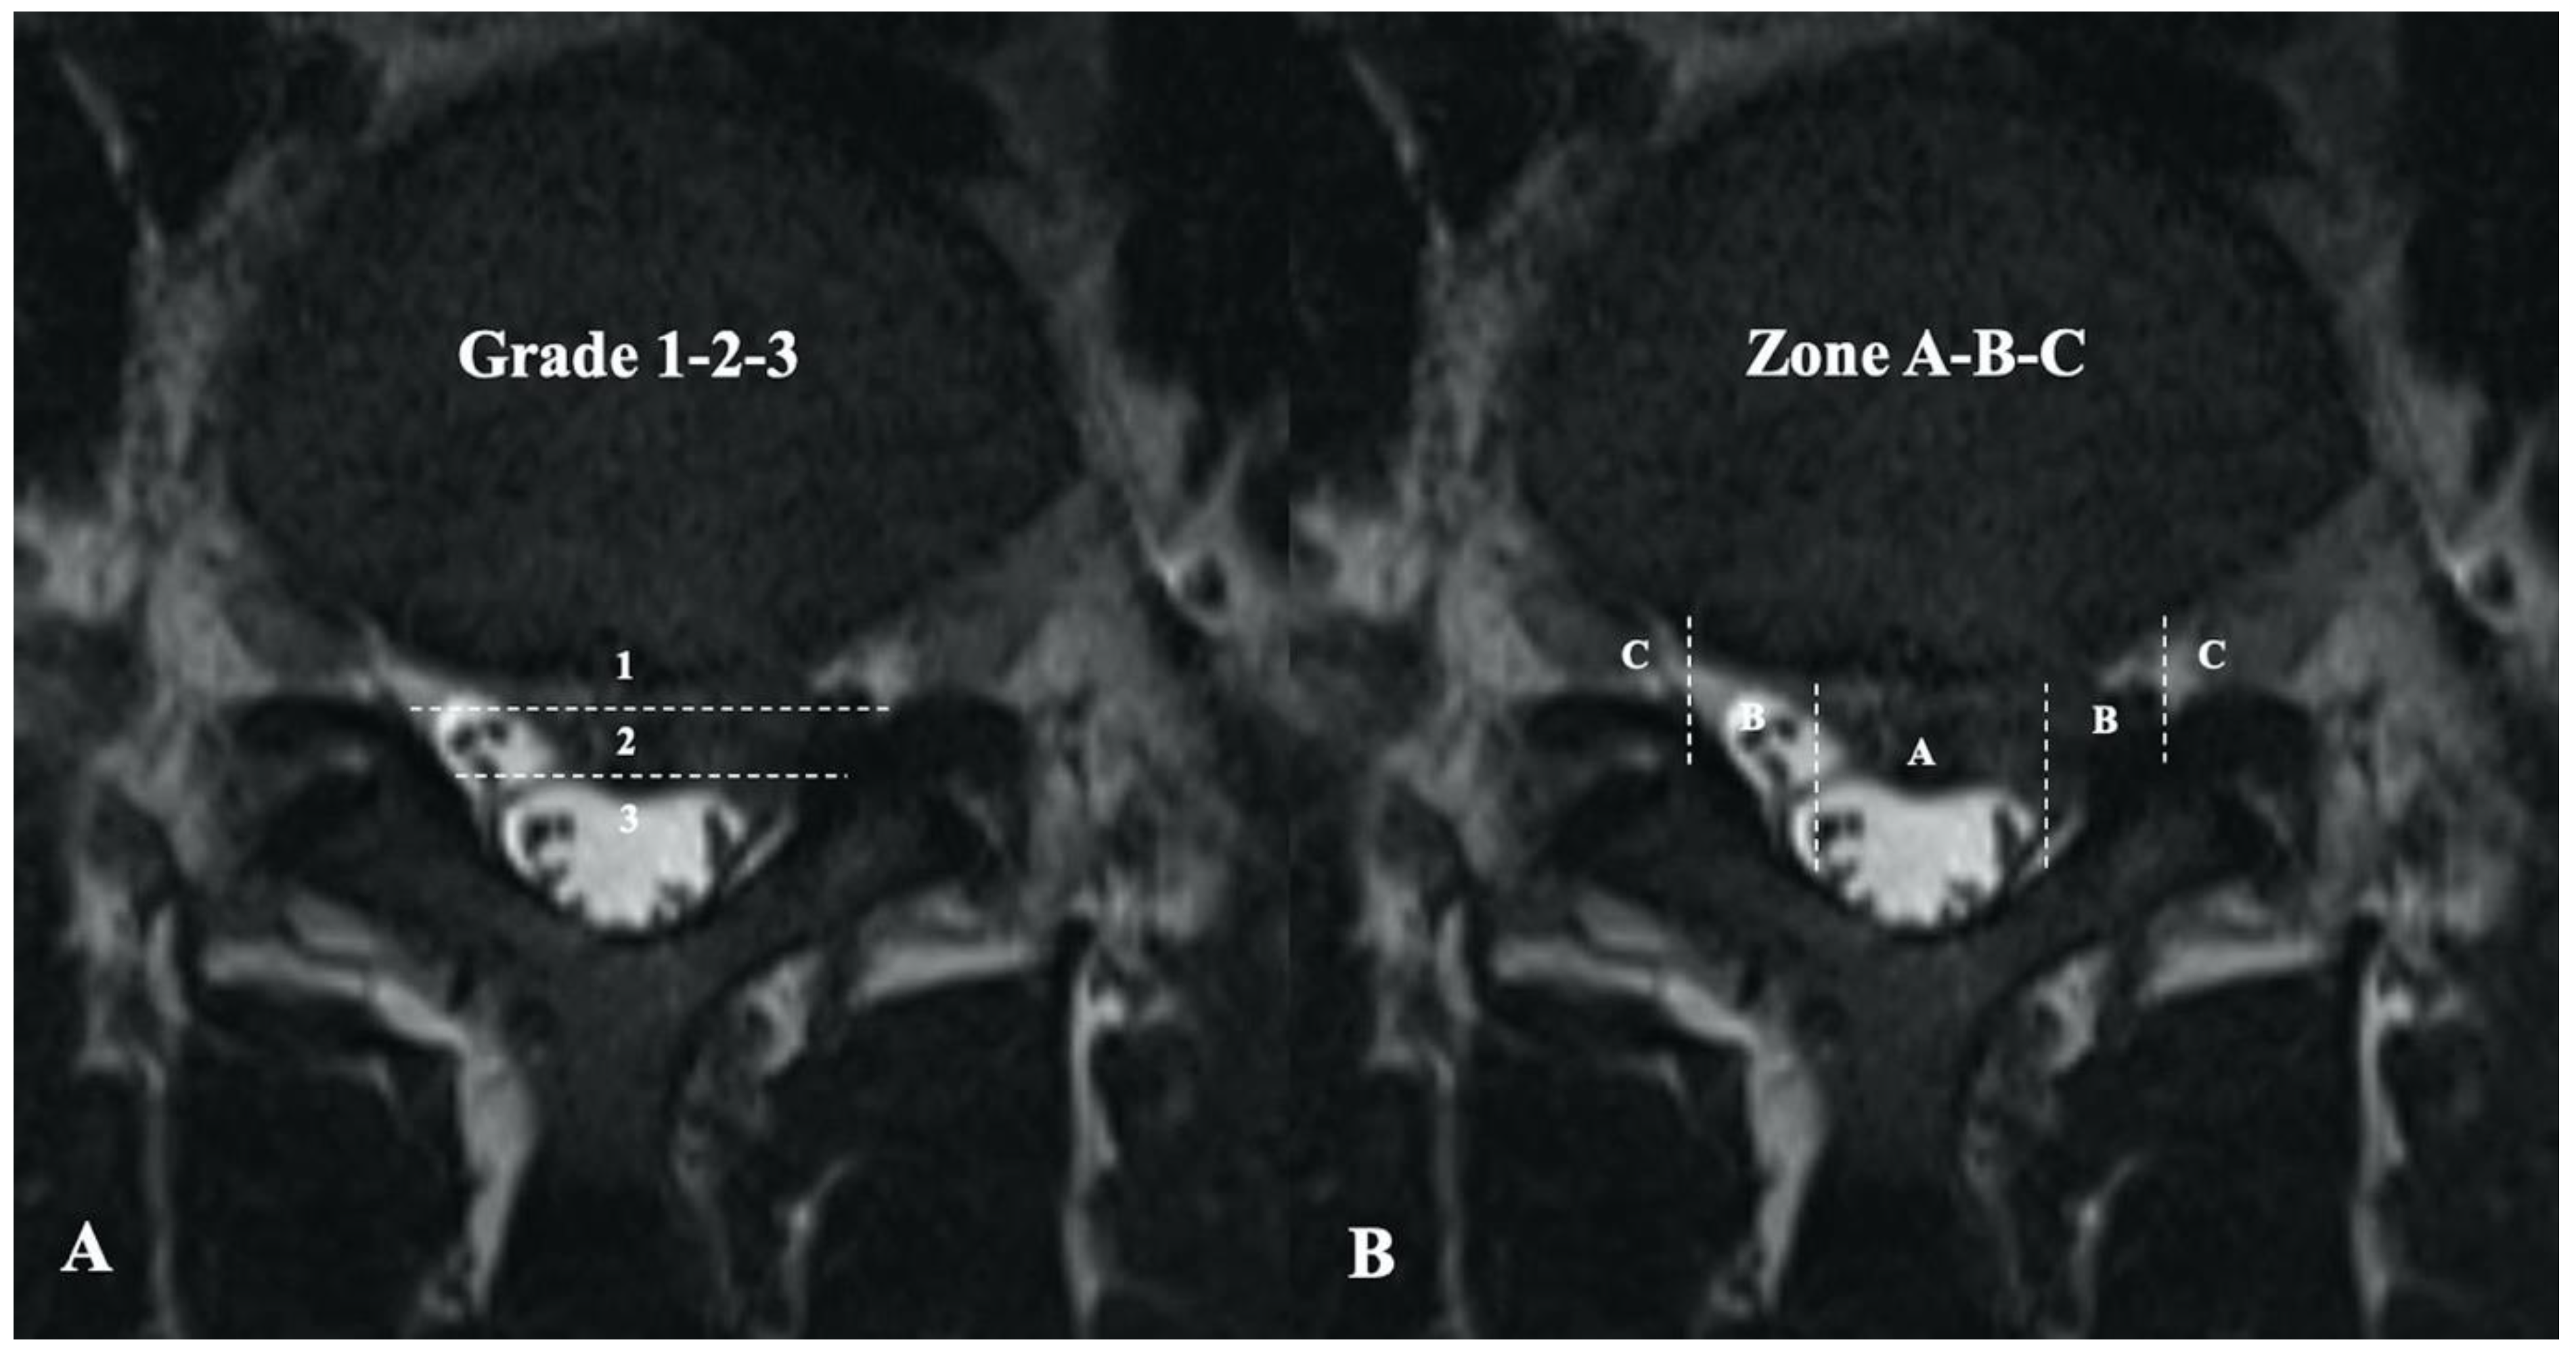

- Mysliwiec, L.W.; Cholewicki, J.; Winkelpleck, M.D.; Eis, G.P. MSU classification for herniated lumbar discs on MRI: Toward developing objective criteria for surgical selection. Eur. Spine J. 2010, 19, 1087–1093. [Google Scholar] [CrossRef] [PubMed]